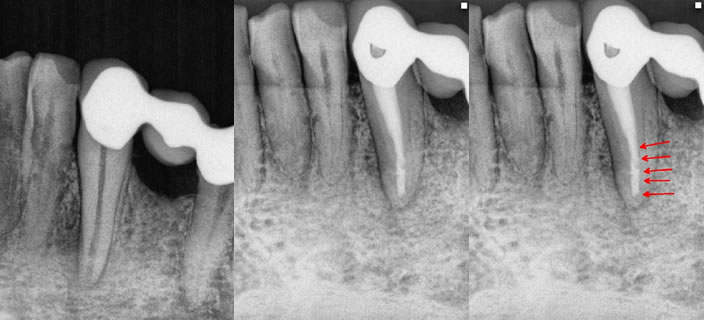

Figure 1

Figure 2: Pre-op radiograph with an apical lesion and an “open” apex. A very important canine tooth and part of a bridge. Figure 3: The immediate post-op following 2.5 months of CaOH treatment. Figure 4: Red arrows indicating the MTA location with gutta percha packed on top of the MTA. There is already a noticable healing response occuring apically as well.